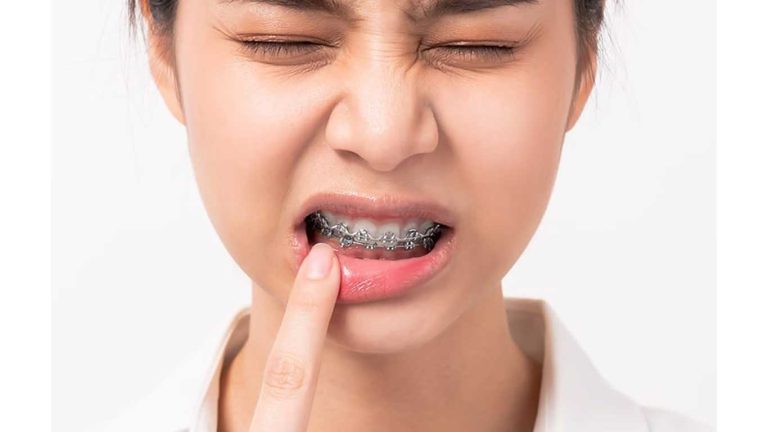

درمان مجدد ارتودنسی ثابت در خانمی ۲۲ ساله که ۱۰ سال قبل توسط همکار دیگر درمان شده بود.

گاهی اوقات بدلایل طبیعی و غیر طبیعی میزان بازگشت در درمان های ارتودنسی زیاد است.

بسیاری از افراد تصور میکنند پس از پایان دوره ارتودنسی، نتیجهای که به دست میآید برای همیشه باقی میماند. اما واقعیت این است که به مرور زمان، به دلایل مختلفی ممکن است دندانها به موقعیت قبلی خود بازگردند. به همین دلیل، درمان مجدد ارتودنسی ثابت برای برخی بیماران ضروری میشود، مخصوصاً اگر ارتودنسی اولیه بیش از ۱۰ سال پیش انجام شده باشد یا از نگهدارندهها بهدرستی استفاده نشده باشد.

گاهی تصور میشود که ارتودنسی درمانی دائمی است و بعد از آن دیگر نیازی به پیگیری یا مراقبت خاصی وجود ندارد. اما حقیقت این است که ساختار دندانها و فکها به مرور زمان ممکن است تحت تأثیر عوامل مختلفی قرار بگیرند و به حالت قبل برگردند. این پدیده که به آن بازگشت درمان ارتودنسی گفته میشود، در بین بیماران شایع است و میتواند علل متعددی داشته باشد:

دلایل طبیعی: رشد مداوم فکها، تغییرات در عضلات صورت، حرکات زبان، و حتی الگوهای تنفسی میتوانند باعث فشار روی دندانها و جابهجایی آنها شوند.

دلایل غیرطبیعی یا قابل پیشگیری: استفاده نکردن از نگهدارنده پس از پایان ارتودنسی، شکستگی یا افتادن ریتینر، یا طراحی نامناسب برنامه درمانی اولیه نیز از مهمترین عوامل برگشت هستند.